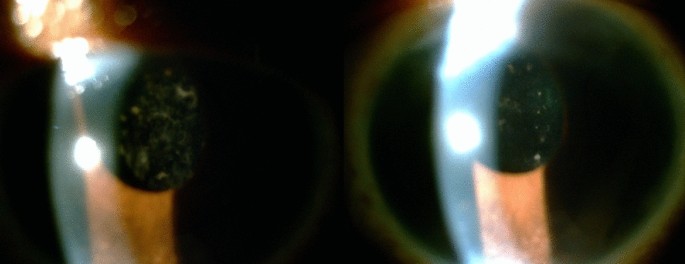

Four months after surgery, 1/20 (5%) patient exhibited anterior chamber cells with opacification of the lens; there was an almost complete improvement in lens opacification and vision after using topical corticosteroids. The patient had a previous history of recurrent anterior idiopathic uveitis (Fig. 2a,b).

As for lens-related complications, one patient presented with cells in the anterior chamber and lens opacification in the fourth month after surgery. Opacification of the Akreos AO60 and other such hydrophilic IOLs has been reported in the literature, including in diabetic patients and in patients with a history of anterior uveitis, and associated with gas tamponade26,27; therefore, some surgeons have changed their preferred IOL to hydrophobic acrylic IOLs, but unfortunately there is no hydrophobic 4-point IOL available in the Brazilian market. In our case, no gas was used intraoperatively, and there was an improvement in the anterior chamber inflammation and lens opacification after using topical corticosteroids. Of note, the patient in our study who presented with anterior chamber cells and lens opacification had a history of recurrent anterior idiopathic uveitis.